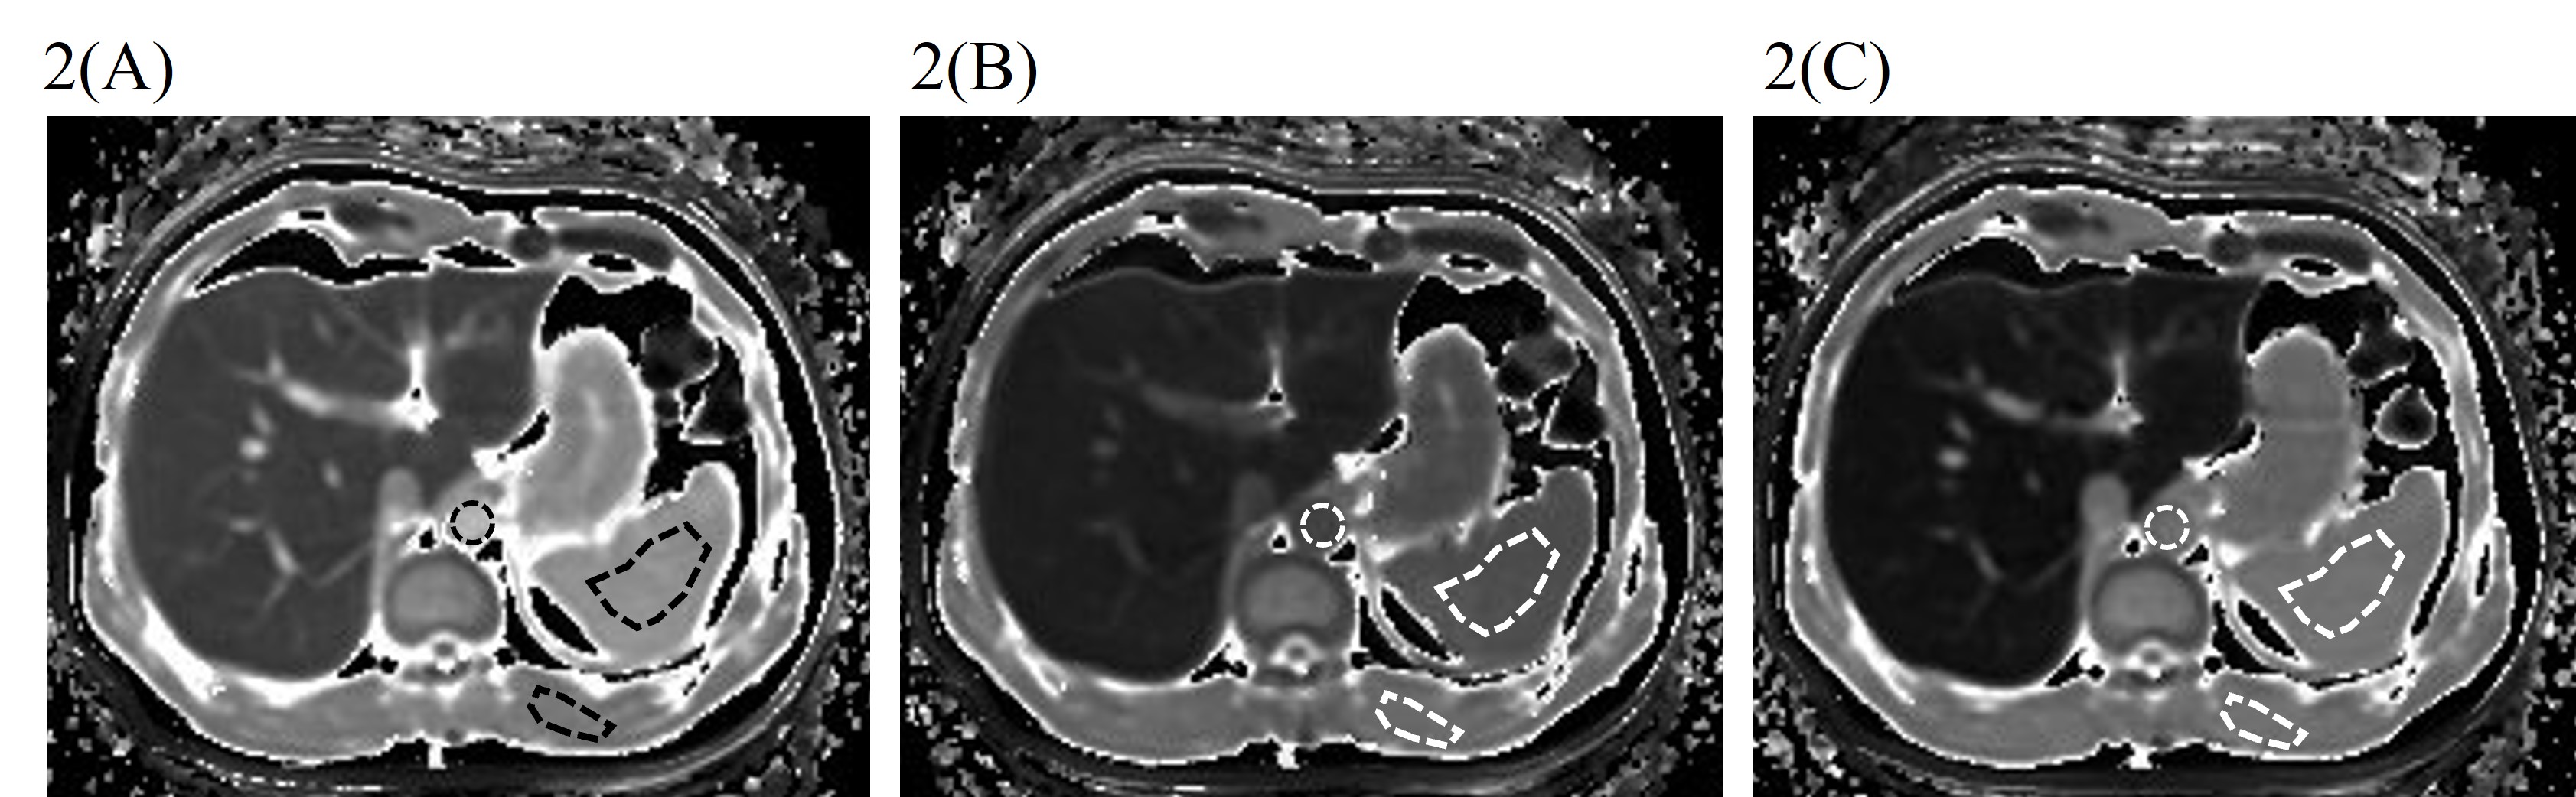

In the phantom study, T1MOLLI values were shown to be strongly dependent on the pattern of heartbeat and recovery time rather than matrix size. T1MOLLI values with 3(3)3(3)3(3)3(3)3 were most close to T1IR values (Table 3). In the clinical study, ECVs obtained from EOB-MRI showed significantly high agreements with those obtained from CT data. Interclass correlation coefficients (ICC) were 0.90 and 0.74 (both p<0.001) for 4min and 25 min images, respectively (Fig. 1). The representative T1 maps before, 4 min after, and 25 min after Gd-EOB-DTPA administration were shown in Fig.2.

Fig. 2: The representative T1 maps before (2A), 4 min after (2B), and 25 min after (2C) Gd-EOB-DTPA administration and position of region of interest (dotted line).